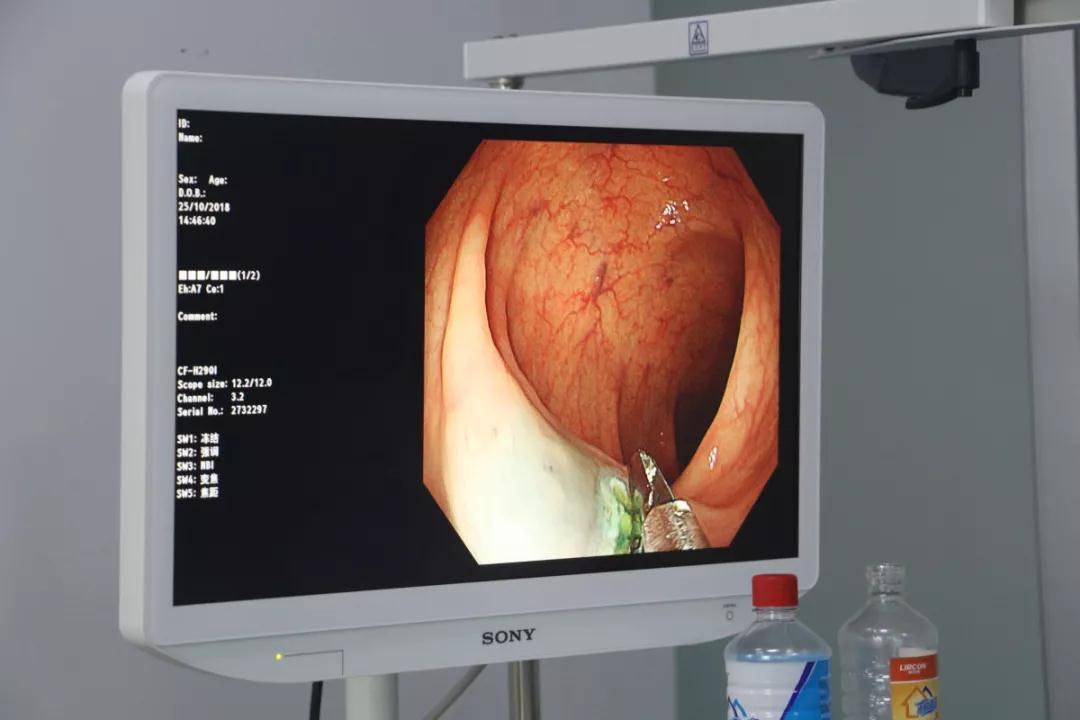

潍坊市人民医院消化科姜鹏飞为患者行结肠息肉EMR切除术

结肠息肉EMR切除术进行中

正值潍坊市人民医院消化科姜鹏飞正在胃镜室值班,向患者家属讲明情况后,并签署知情同意书,在人民医院专家的配合下,当即为患者行结肠息肉EMR切除术,手术非常成功,患者术中无明显不适,术后很快进食,无不适感。查房时将检查结果告知患者并进行了详细的解释,他都倒吸一口冷气,“我这不是癌吧”“不是,你这个是息肉,切了就没事了,但如果不切除,很有可能会变成癌。”这时他才说起,他父亲和姐姐都是因为这个病去世的,刚开始他也有过担心,由于父亲和姐姐做肠镜的时候非常痛苦,自己就没敢做,时间长了,慢慢把这个事淡忘了,患者经过息肉切除术后去除了癌症的风险。